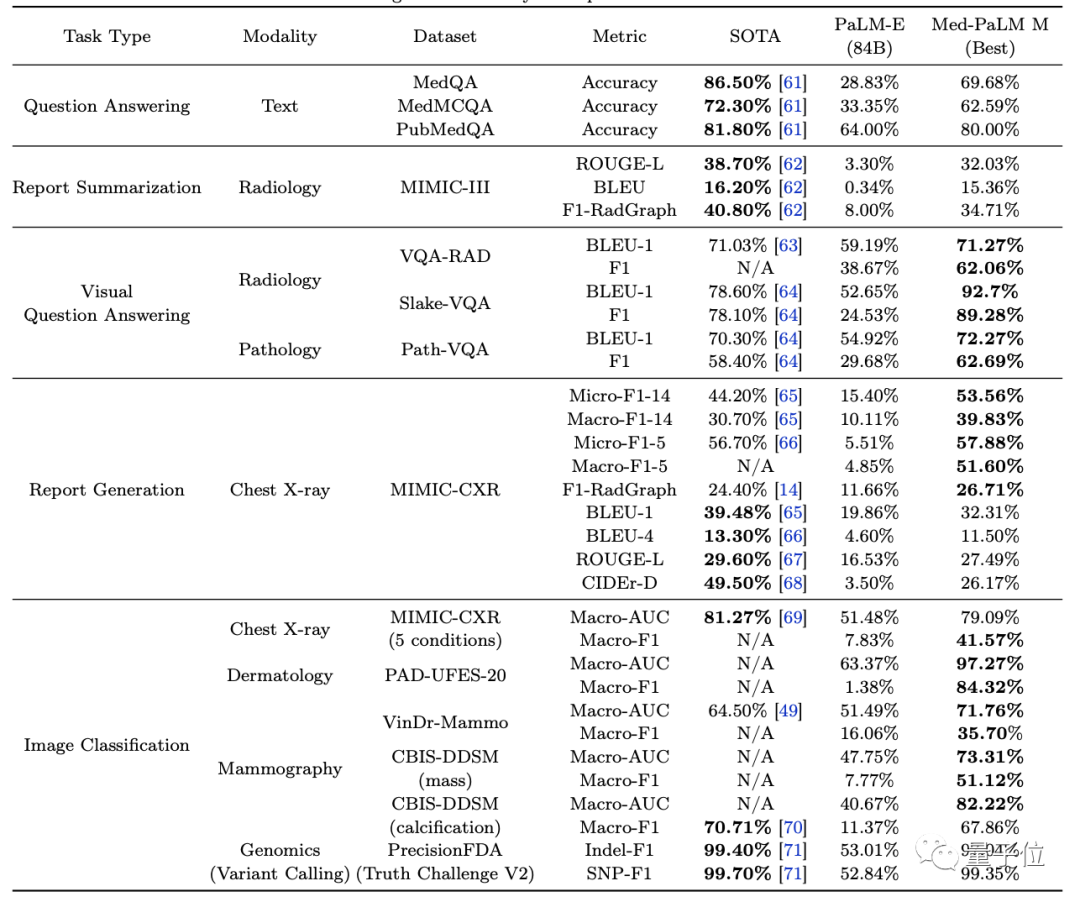

(1)与专业SOTA模型和无生物医学领域微调的广义模型(PaLM-E 84B)相比,Med-PaLM M在MultiMedBench上的所有任务、数据集和指标组合(共计14项)中,性能均基本接近SOTA或超过SOTA。

需要注意的是,该结果是在没有任何特定任务定制的情况下使用相同的模型权重集实现的。

(2)在scale实验中,三个不同规模的Med-PaLM M对各类任务的影响各不相同:

粗略来看,对于纯语言任务和需要调整的多模式任务来说,模型越大越好;但对图像分类和胸部X光报告生成任务来说,84B的效果比562B表现反而更好一些。